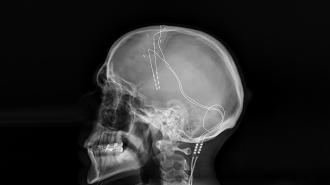

To deliver the treatment, a surgeon implants one or more electrodes into a patient’s brain. A small battery-powered pulse generator, generally placed under the skin near the patient’s collarbone, then sends an electrical current to the electrodes via an implanted wire.

It’s designed so that the natural inflation of a person’s lungs would press on an implanted “nanogenerator” that converts the movement into static electricity. The current from the nanogenerator charges a supercapacitor, which then powers the deep brain stimulator.